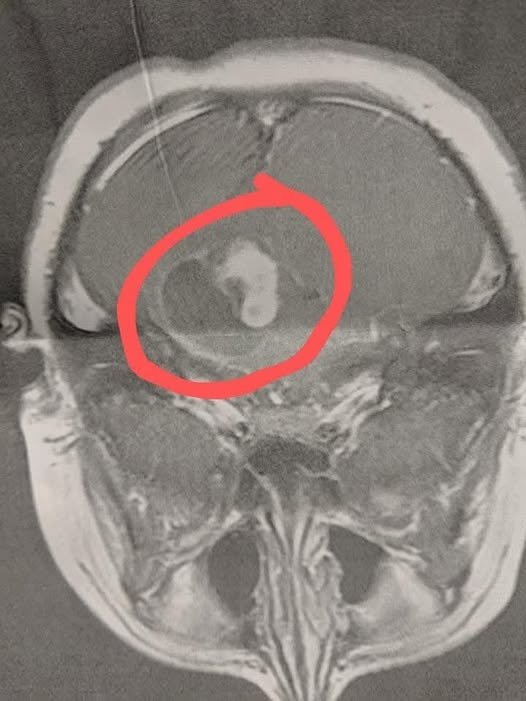

On the way home, I got a call from the pediatrician telling me to come in immediately for the results. In that moment, I knew something was very wrong. The MRI showed a large brain tumor with fluid around it. My son had emergency surgery at Duke that same day. The operation lasted 8 hours. The surgeon was able to remove 90% of the tumor, but the remaining 10% was on his brain stem and too dangerous to remove.

Six weeks later, we did a follow-up MRI to see how things were healing, and we received devastating news — the tumor had grown back. My son started chemotherapy right away and went through a full year of intense treatment. Today, he has been stable for 3 years.